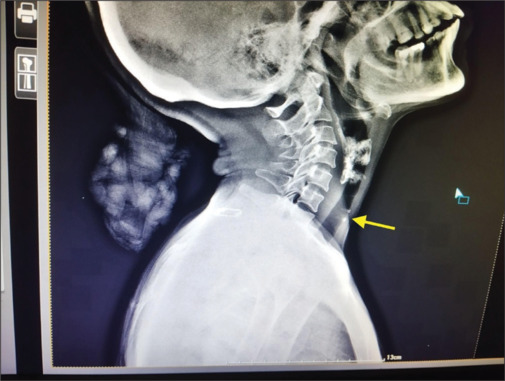

This article highlights a unique case of Plummer-Vinson syndrome (PVS), also known as Paterson Brown-Kelly Syndrome. PVS is associated with a triad of symptoms, including microcytic hypochromic anemia, esophageal strictures, and dysphagia. It is commonly found in middle-aged women, particularly in the fourth and fifth decades of life, and is rarely reported in males. We present the case of a 49-year-old female patient who exhibited the classic symptoms of PVS. Given that PVS is a precancerous condition with a high potential for malignancy, early diagnosis is crucial for a better prognosis. Surveillance endoscopy and barium swallow test are recommended for monitoring. Iron repletion often improves dysphagia, and in some cases, esophageal dilatation is used to provide symptomatic relief. The mutual interaction of systemic and oral health is often underestimated, especially by patients in developing countries. Therefore, this report emphasizes the importance of thorough medical history taking and its relevance to dental health and treatment.